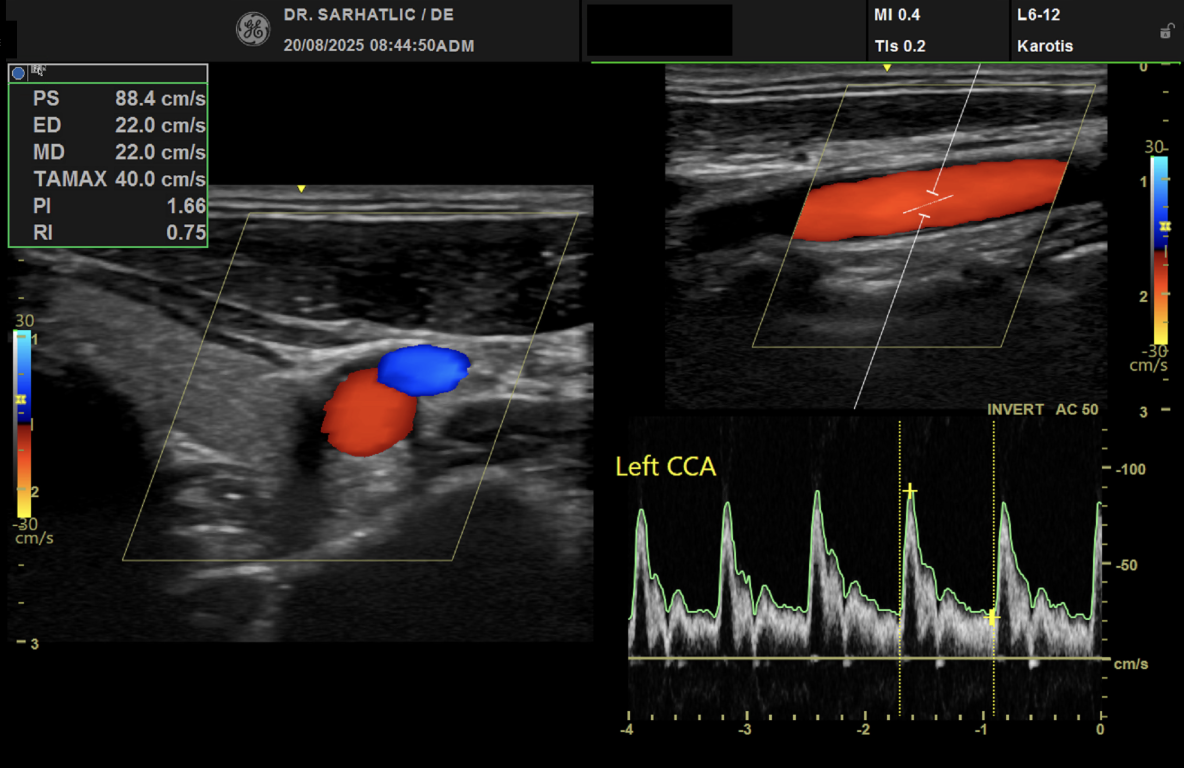

MODERNE ULTRASCHALLDIAGNOSTIK- Modernes Farbdoppler-Ultraschallgerät

- Hochauflösende Schallköpfe

- Ultraschall der Gefäße (z. B. Halsschlagadern)

- Schlaganfallvorsorge (inkl. Gefäßdiagnostik)